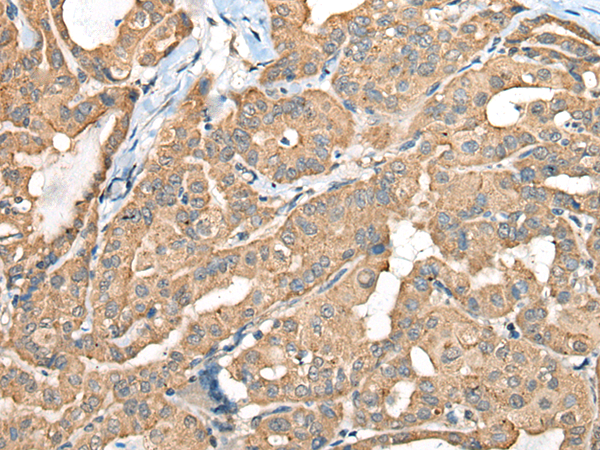

ELISA, IHC |

IHC positive control: |

Human thyroid cancer |

IHC Recommend dilution: |

40-200 |